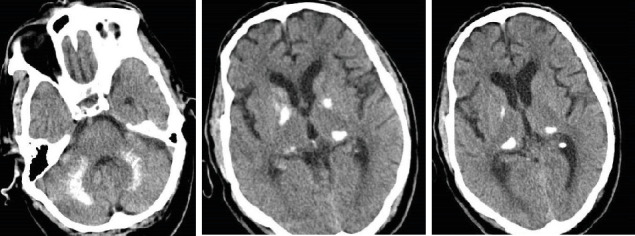

Background: Fahr's syndrome is a rare neurodegenerative condition characterized by bilateral progressive calcification of the basal ganglia and other brain structures. Due to overlapping symptoms, it can be misdiagnosed as other neurological disorders. Case presentation: A 68-year-old man was presented to the emergency department with an exacerbating decline in the level of consciousness and dysarthria over a 20-day period. On admission, the laboratory examinations revealed a low level of calcium and parathyroid hormone. Brain imaging findings showed bilateral calcifications in the basal ganglia, pulvinar region of the thalami, and dentate nuclei. In addition, a prolonged QTc interval on his electrocardiogram (ECG) indicated hypocalcemia. After receiving calcium gluconate 10%, the calcium level and QTc interval stabilized, and the patient's level of consciousness gradually improved. Conclusion: Fahr's syndrome due to hypoparathyroidism should be suspected in any patient with neurological symptoms and hypocalcemia. Hence, early identification and management of hypoparathyroidism can prevent progression of calcification and improve patients' quality of life and prognosis.